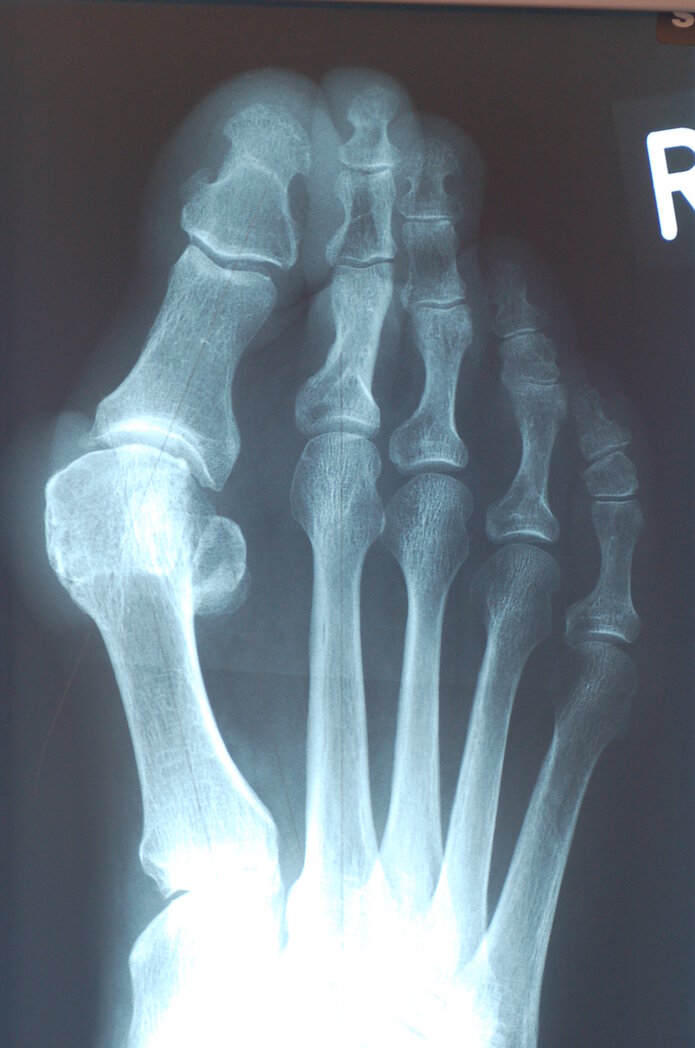

Beim Hallux valgus handelt es sich um die häufigste Fehlstellung des Vorfußes und der Zehen. Während bei einem gesunden Fuß die Zehenknochen gerade ausgerichtet sind, neigt sich bei einem Hallux valgus das Grundgelenk der Großzehe nach außen. Durch diese Abspreizung des ersten Mittelfußknochens wird der Fuß breiter. An seiner Innenseite wird eine mehr oder weniger große und charakteristische Wölbung am Großzehengrundgelenk sichtbar. Unbehandelt verändert die Großzehe zunehmend ihre Ausrichtung und schiebt sich über oder unter die Kleinzehen. Sie verdrängt diese aus ihrer natürlichen Position, was zu weiteren Fußdeformitäten führt.